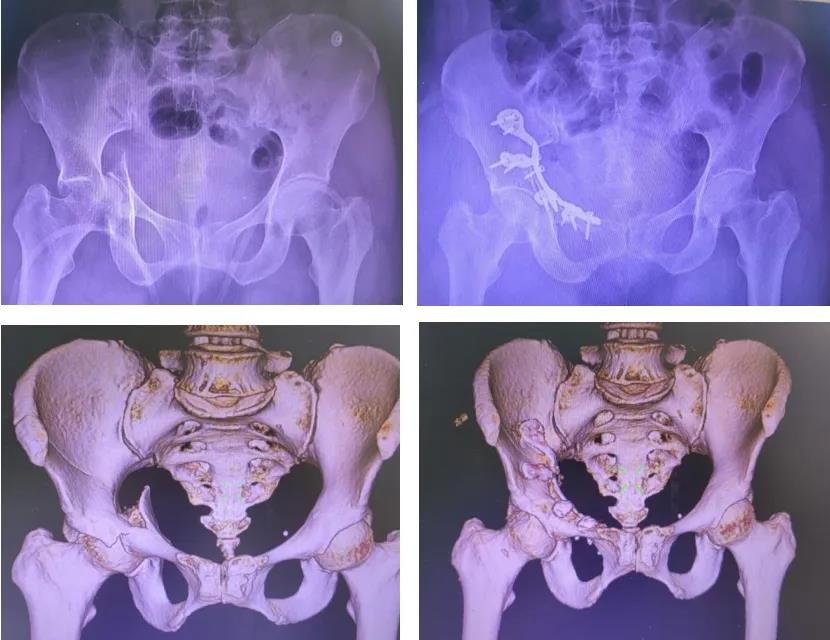

▲术前与术后影像学对比

2025年12月30日,在麻醉团队与手术室团队高效配合下,由李振宏主任领衔的骨盆专科团队为韦阿姨实施右髋臼骨折、骨盆骨折切开复位内固定手术。术中,计划中的5.5厘米小切口被精确打开。医生们凭借对局部解剖的深刻理解,在肌肉与髂外血管鞘的缝隙中娴熟操作,迅速而稳妥地建立了直达骨折端的工作通道。通过这个有限的窗口,借助高亮度的冷光源与移动窗视野,髋臼方形区移位的骨块清晰呈现。在术中C臂机的实时扫描监控下,医生利用特殊的复位器械,如同进行一场微观世界的拼图,将每一块重要的骨块精确复位。随后,一块依据韦阿姨骨骼形态预弯成型的髋臼一体化蝶形钢板植入,多枚螺钉经预设的安全通道牢牢固定。手术切口仅5.5cm,术中出血不到400ml,生命体征平稳,手术时长约80分钟。

微创手术带来的益处在术后即刻显现。由于肌肉软组织损伤极小,韦阿姨髋臼骨折处疼痛明显改善,疼痛评分显著低于传统手术患者,髋关节屈伸功能正常,可自主在床上翻身活动,饮食、精神状态等恢复较快,术后第3天便能在床上坐起,状态佳,气色好。复查骨盆X线和CT三维重建显示骨盆髋臼骨折复位固定良好。若后期康复训练到位,韦阿姨有望三个月后重新站立行走。